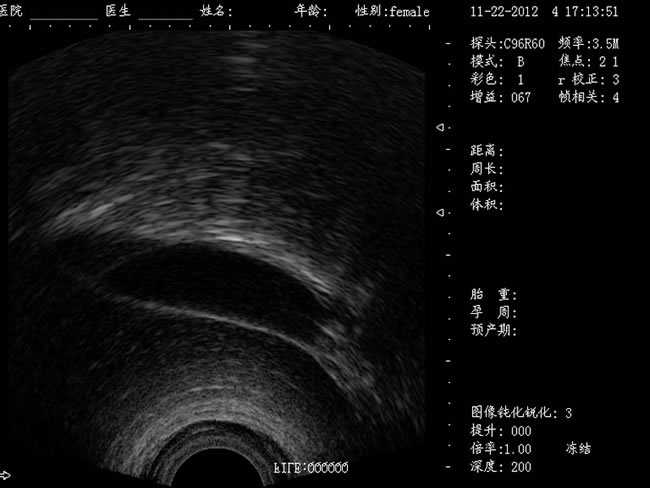

定位精確 手術(shù)效率高:實(shí)時(shí)動(dòng)態(tài)頻率掃描等全數(shù)字超聲成像技術(shù)、生成精確的圖像引導(dǎo)手術(shù)器械迅速到大手術(shù)位置,避免損傷子宮內(nèi)膜和子宮穿孔的現(xiàn)象,即減輕了患者的痛苦又極大提高了手術(shù)效率。

有效提升系統(tǒng)的穩(wěn)定性、可靠性:實(shí)時(shí)動(dòng)態(tài)孔徑成像,充分保證圖像的精度和清晰度

CXA10R/6.5MHz 腔內(nèi)探頭